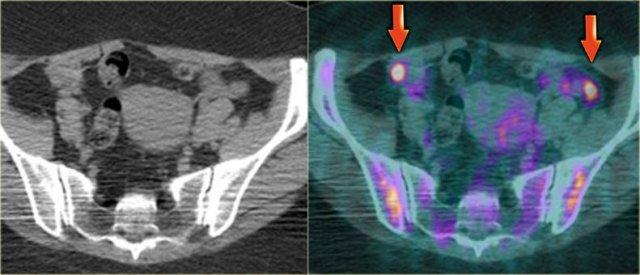

Bẫy chẩn đoán trên FDG-PET – buồng trứng bình thường ở phụ nữ tiền mãn kinh

Ở một số phụ nữ tiền mãn kinh, buồng trứng bình thường có thể bắt FDG mạnh trên PET, tùy thuộc vào thời điểm trong chu kỳ kinh nguyệt.

Do ở phụ nữ tiền mãn kinh, buồng trứng dương tính trên PET có thể là u phần phụ hoặc hoàn toàn bình thường, điều quan trọng là phải nhận thức được khả năng bắt FDG sinh lý vào giữa chu kỳ và cần đối chiếu với bệnh sử lâm sàng.

Do đó, FDG-PET ở phụ nữ tiền mãn kinh nên được lên lịch ưu tiên vào tuần đầu tiên của chu kỳ kinh nguyệt.

Ở phụ nữ hậu mãn kinh, buồng trứng bình thường chỉ bắt FDG tối thiểu.

Bất kỳ sự tăng bắt FDG tại buồng trứng nào ở nhóm tuổi này đều gợi ý khả năng có u tân sinh.